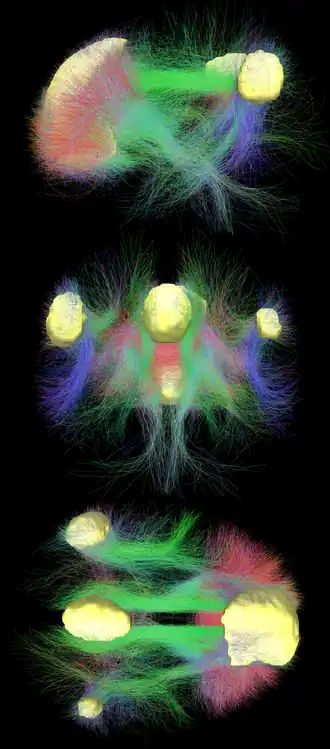

Diffusion MRI imaging shows white matter tracts connecting different areas of the DMN together.[22] The structural connections found from diffusion MRI imaging and the functional correlations from resting state fMRI show the highest level of overlap and agreement within the DMN areas.[1] This provides evidence that neurons in the DMN regions are linked to each other through large tracts of axons and this causes activity in these areas to be correlated with one another. From the point of view of effective connectivity, many studies have attempted to shed some light using dynamic causal modeling, with inconsistent results. However, directionality from the medial prefrontal cortex towards the posterior cingulate gyrus seems confirmed in multiple studies, and the inconsistent results appear to be related to small sample size analysis.[28]